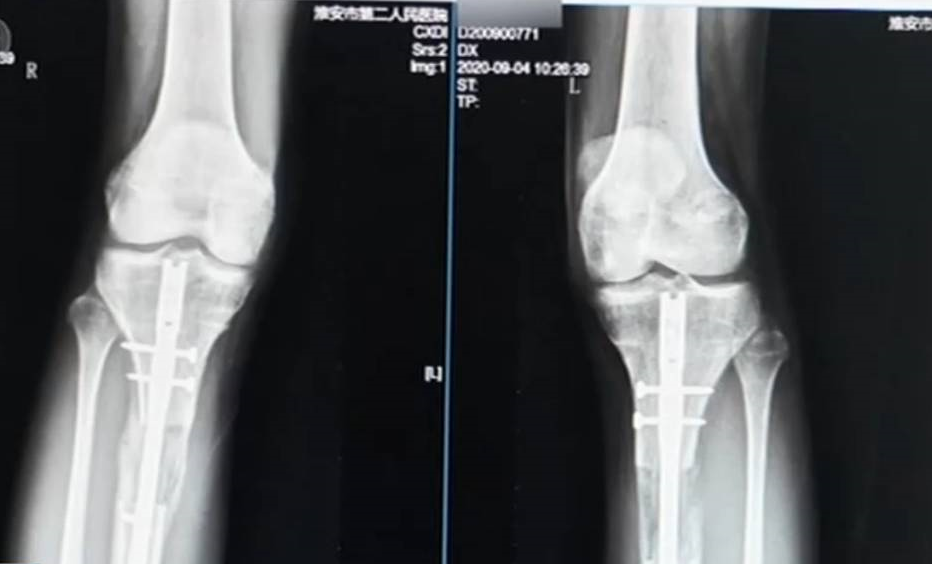

雖不時耳聞「斷骨增高」手術的風險,但卻還是有人願意為了長高豪賭一把。近日在大陸江蘇淮安有一名22歲的少男在奶奶的陪同下,到淮安第二人民醫院找醫生求救,據悉這名患者當時已無法行走,雙腿嚴重感染。陸媒報導,這名患者因自己身高不滿180公分,2019年底遠赴韓國做斷骨增高手術,不料術後復原狀況不佳,手術副作用明顯,讓他無法走路。淮安第二人民醫院的骨科醫師表示:「患者腿部外固定支架的釘道出現了嚴重的感染,進一步引發骨髓炎。」

「斷骨增高」手術顧名思義就是將骨頭打斷再使其延伸,但就算成功,也恐怕會留下各種後遺症,得不償失。 醫師指出,這個手術對於患者而言不僅失敗,更帶給患者非常大的經濟負擔。除此之外,還可能造成終身殘疾。